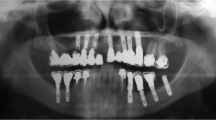

The research material concerns two types of implants: single- (replace implant) and double-threaded (active implant) dental materials possess the ability to compact the bone. The first of them was introduced for 108 patients (51 in the maxillary and 57 in the mandibular bone), while the second for 38 patients (35 in the maxillary and 5 in the mandibular bone). The photographs were not distinguished by gender, as the number of individual groups obtained as a result would be too small to carry out reliable analyses. Images of the implant zones were performed directly after introduction and after 12 months of prosthetic loading (Fig. 1). From the received images, apart from the implant area, areas of healthy, intact bone were used (31 figures from the maxillary and 28 from the mandibular bone). These radiographic images were assigned to the following comparison groups:

Preparation of images for analysis was performed in four stages (Fig. 1):

All these operations were carried out in ImageJ, the intended program for image processing and analysis. For all RVG images, rectangular regions of interest with similar dimensions were selected on both sides of the implant. Based on the literature, a bilinear interpolation method was used for the rotation [33, 37]. Histogram operations were used to attempt improve the quality digitized image [17, 20]. The images after processing in ImageJ were then analyzed in the Qmazda program. No normalization was performed with this program. As a result of actions in this program, almost 600 texture features values were extracted on the basis of ROI of each image.